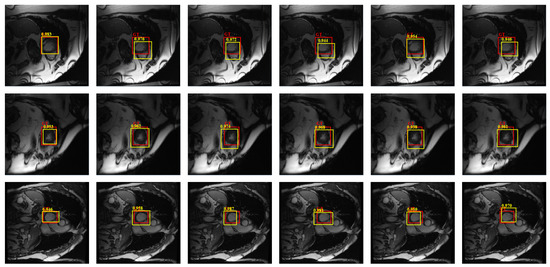

2.6. Refinement

4.4.1. Detection Performance